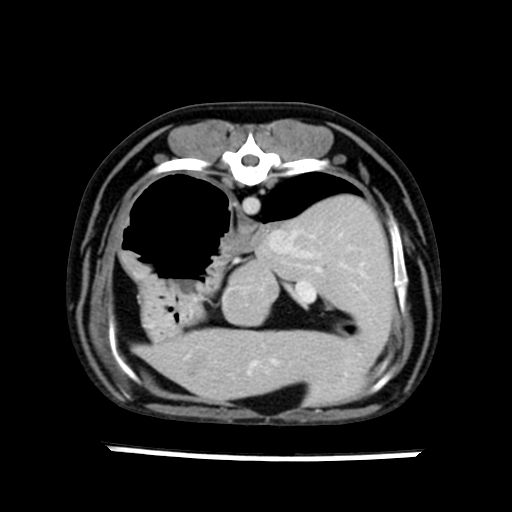

prescritto esame TAC

sequenza immagini limitata al fegato reni e surreni

le immagini ecografiche rispetto alla tac datano circa 7 mesi prima ,le surrenali sono normali nonostante il test acth sia risultato positivo .all’esame TAC dopo diversi mesi risultano aumentate armonicamente nel volume e si individua un forte sospetto di adenoma ipofisario .

sospetto adenoma ipofisario vs. meno probabilmente meningioma della base; intertiziopatia polmonare; lesione espansiva epatica, verosimilmente del lobo laterale sinistro, di sospetta natura neoplastica; lesioni spleniche di natura da definire; iperplasia/ipertrofia delle ghiandole surrenali, bilateralmente; vertebra di transizione del rachide toracico; tenosinovite cronica del muscolo bicipite brachiale di destra.